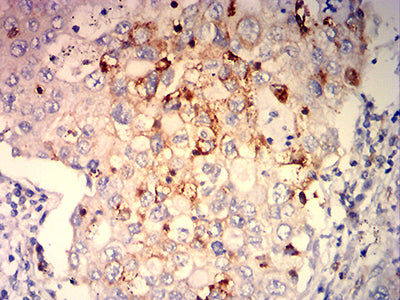

分类: 科研抗体货号: 32270别名: CMH2; RCM3; TnTC; cTnT; CMD1D; CMPD2; LVNC6应用: IHC,FCM反应种属: Human